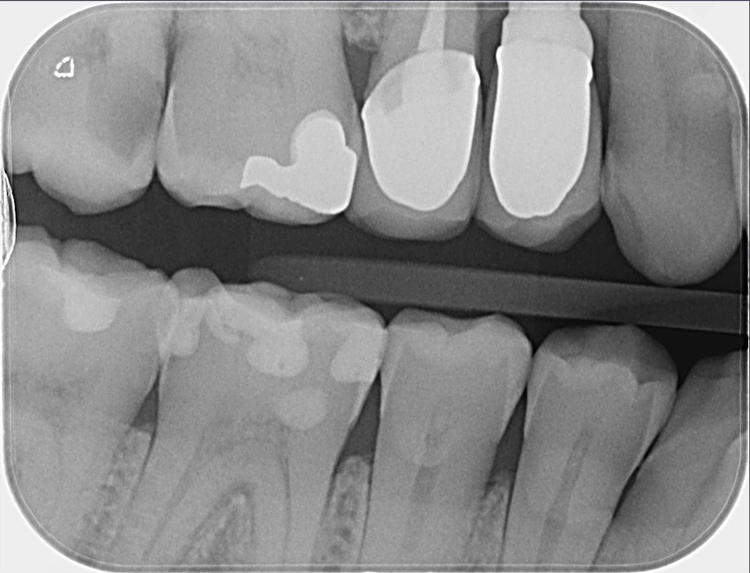

Falls gewünscht, können die maschinell detektierten Befunde vom Behandler angepasst oder ergänzt werden. Anschließend stehen Befund und Therapieempfehlung für das Patientengespräch bereit. Da dentalXrai die Detektion farblich hervorhebt, ist sie auch für den Patienten am iPad verständlich und nachvollziehbar (Abb. 3–6). Ein automatisch erstelltes Gesprächsprotokoll mit der dentalXrai-Befundung kann dem Patienten ganz einfach per verschlüsselter Mail geschickt werden.

dentalXraiAbb. 3–6: Der Vergleich von nativem Röntgenbild (am Beispiel von OPG und Bissflügelaufnahme verschiedener Patienten) und dem Bild mit eingeblendeten Detektionen zeigt die Gründlichkeit der KI-Befundung. Die befundeten apikalen Läsionen sind orangefarben markiert, die Karies rot. Bestehende Versorgungen sind blau und türkis hervorgehoben. Die Zahnsituation ist so für den Patienten im Gespräch gut nachvollziehbar und auch in der Nachbereitung zuhause immer wieder gut zu erkennen.